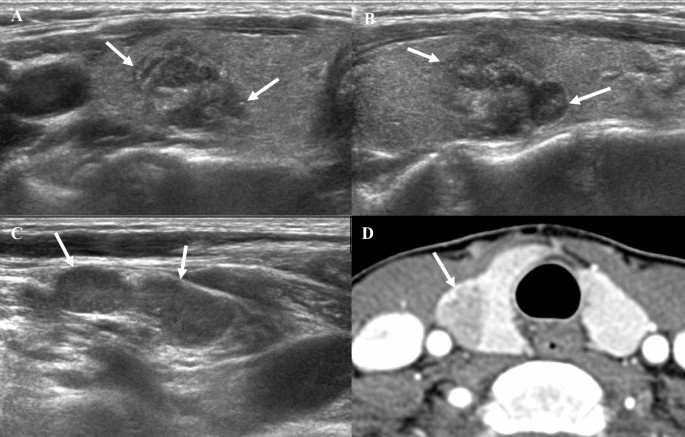

When comparing US features based on survival period, nodules in patients with a survival period of less than 12 months were larger (5.17 ± 1.49 cm vs. 3.95 ± 1.63 cm, p = 0.005) and more likely to be suspicious for gross ETE on US (91.43% vs. 69.57%, p = 0.04) (Table 2, Fig. 3 and Fig. 4). Other US features, such as composition, echogenicity, margin, orientation, echogenic foci, heterogeneity, lobulation, K-TIRADS, and ACR TI-RADS, did not significantly differ between the two groups (p > 0.05).

A 56-year-old woman diagnosed with anaplastic thyroid carcinoma, confirmed to be negative for TERT promoter mutation. (A, B) The transverse and longitudinal US images reveal a 1.8 cm irregular, heterogeneous hypoechoic nodule with punctate echogenic foci in the right thyroid gland (arrows). The nodule is intrathyroidally located, and gross extrathyroidal extension (ETE) was not suspected on US. (C) Multiple metastatic lymph nodes are observed in the ipsilateral neck (arrow). (D) The axial contrast-enhanced CT image demonstrates a low-density mass in the right thyroid gland without evidence of ETE (arrow). There was no indication of distant metastasis at diagnosis. A total thyroidectomy with central neck dissection and right lateral neck dissection was performed, which revealed no pathological ETE. The patient remains alive, with a survival period of 59.77 months from diagnosis to the most recent follow-up, without recurrence. CT, computed tomography; TERT, telomerase reverse transcriptase; US, ultrasonography.